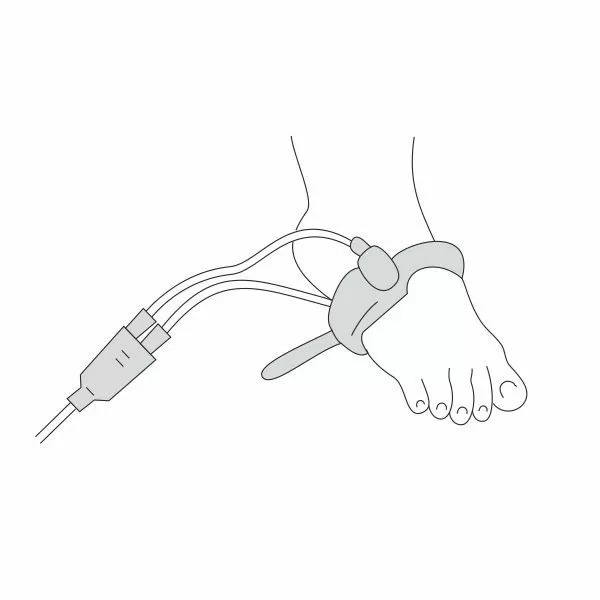

Почему может врать пульсоксиметр?

Причин, по которым пульсоксиметр может проводить измерения неверно, бывает несколько:

- у вас холодные руки. Согрейте их перед измерением;

- вы не до конца поместили палец внутрь прибора или измерению мешает длинный ноготь. Толстый слой гель-лака тоже может быть препятствием;

- вы долго находились в медицинской маске. Снимите ее, подышите глубоко и после этого делайте замер.